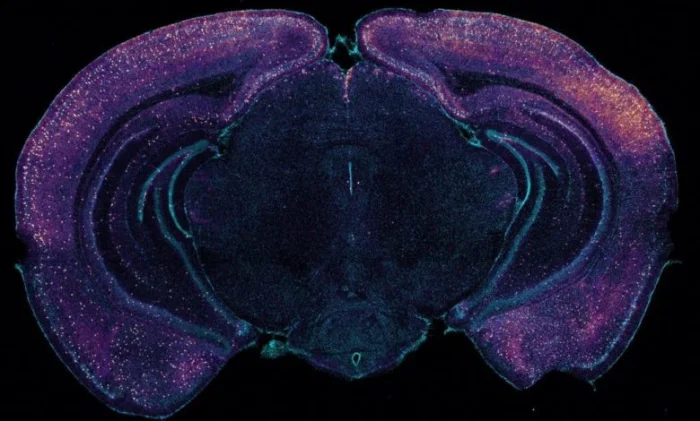

Чтобы подтвердить свою гипотезу, исследователи использовали мышиные модели болезни Альцгеймера. Для воспроизведения результатов предыдущих исследований они вводили мультисенсорные симуляторы с частотой 40 Герц. Затем они наблюдали за корреляционными изменениями в жидкостях, циркулирующих через глимфатическую систему. Они обнаружили, что объемы СМЖ (в тканях мозга) и интерстициальной жидкости (выходящей из мозга) у леченых мышей увеличились по сравнению с контрольными (нелечеными). Также наблюдалось расширение лимфатических сосудов, отводящих эти жидкости. Это привело к накоплению амилоидных белков в лимфатических узлах головного мозга, которые фильтруют жидкость для удаления отработанных продуктов. Кроме того, у обработанных мышей наблюдалось увеличение пульсации артерий. Картинка начинает складываться: стимуляция словно «прокачивает» насосы, отвечающие за чистоту.